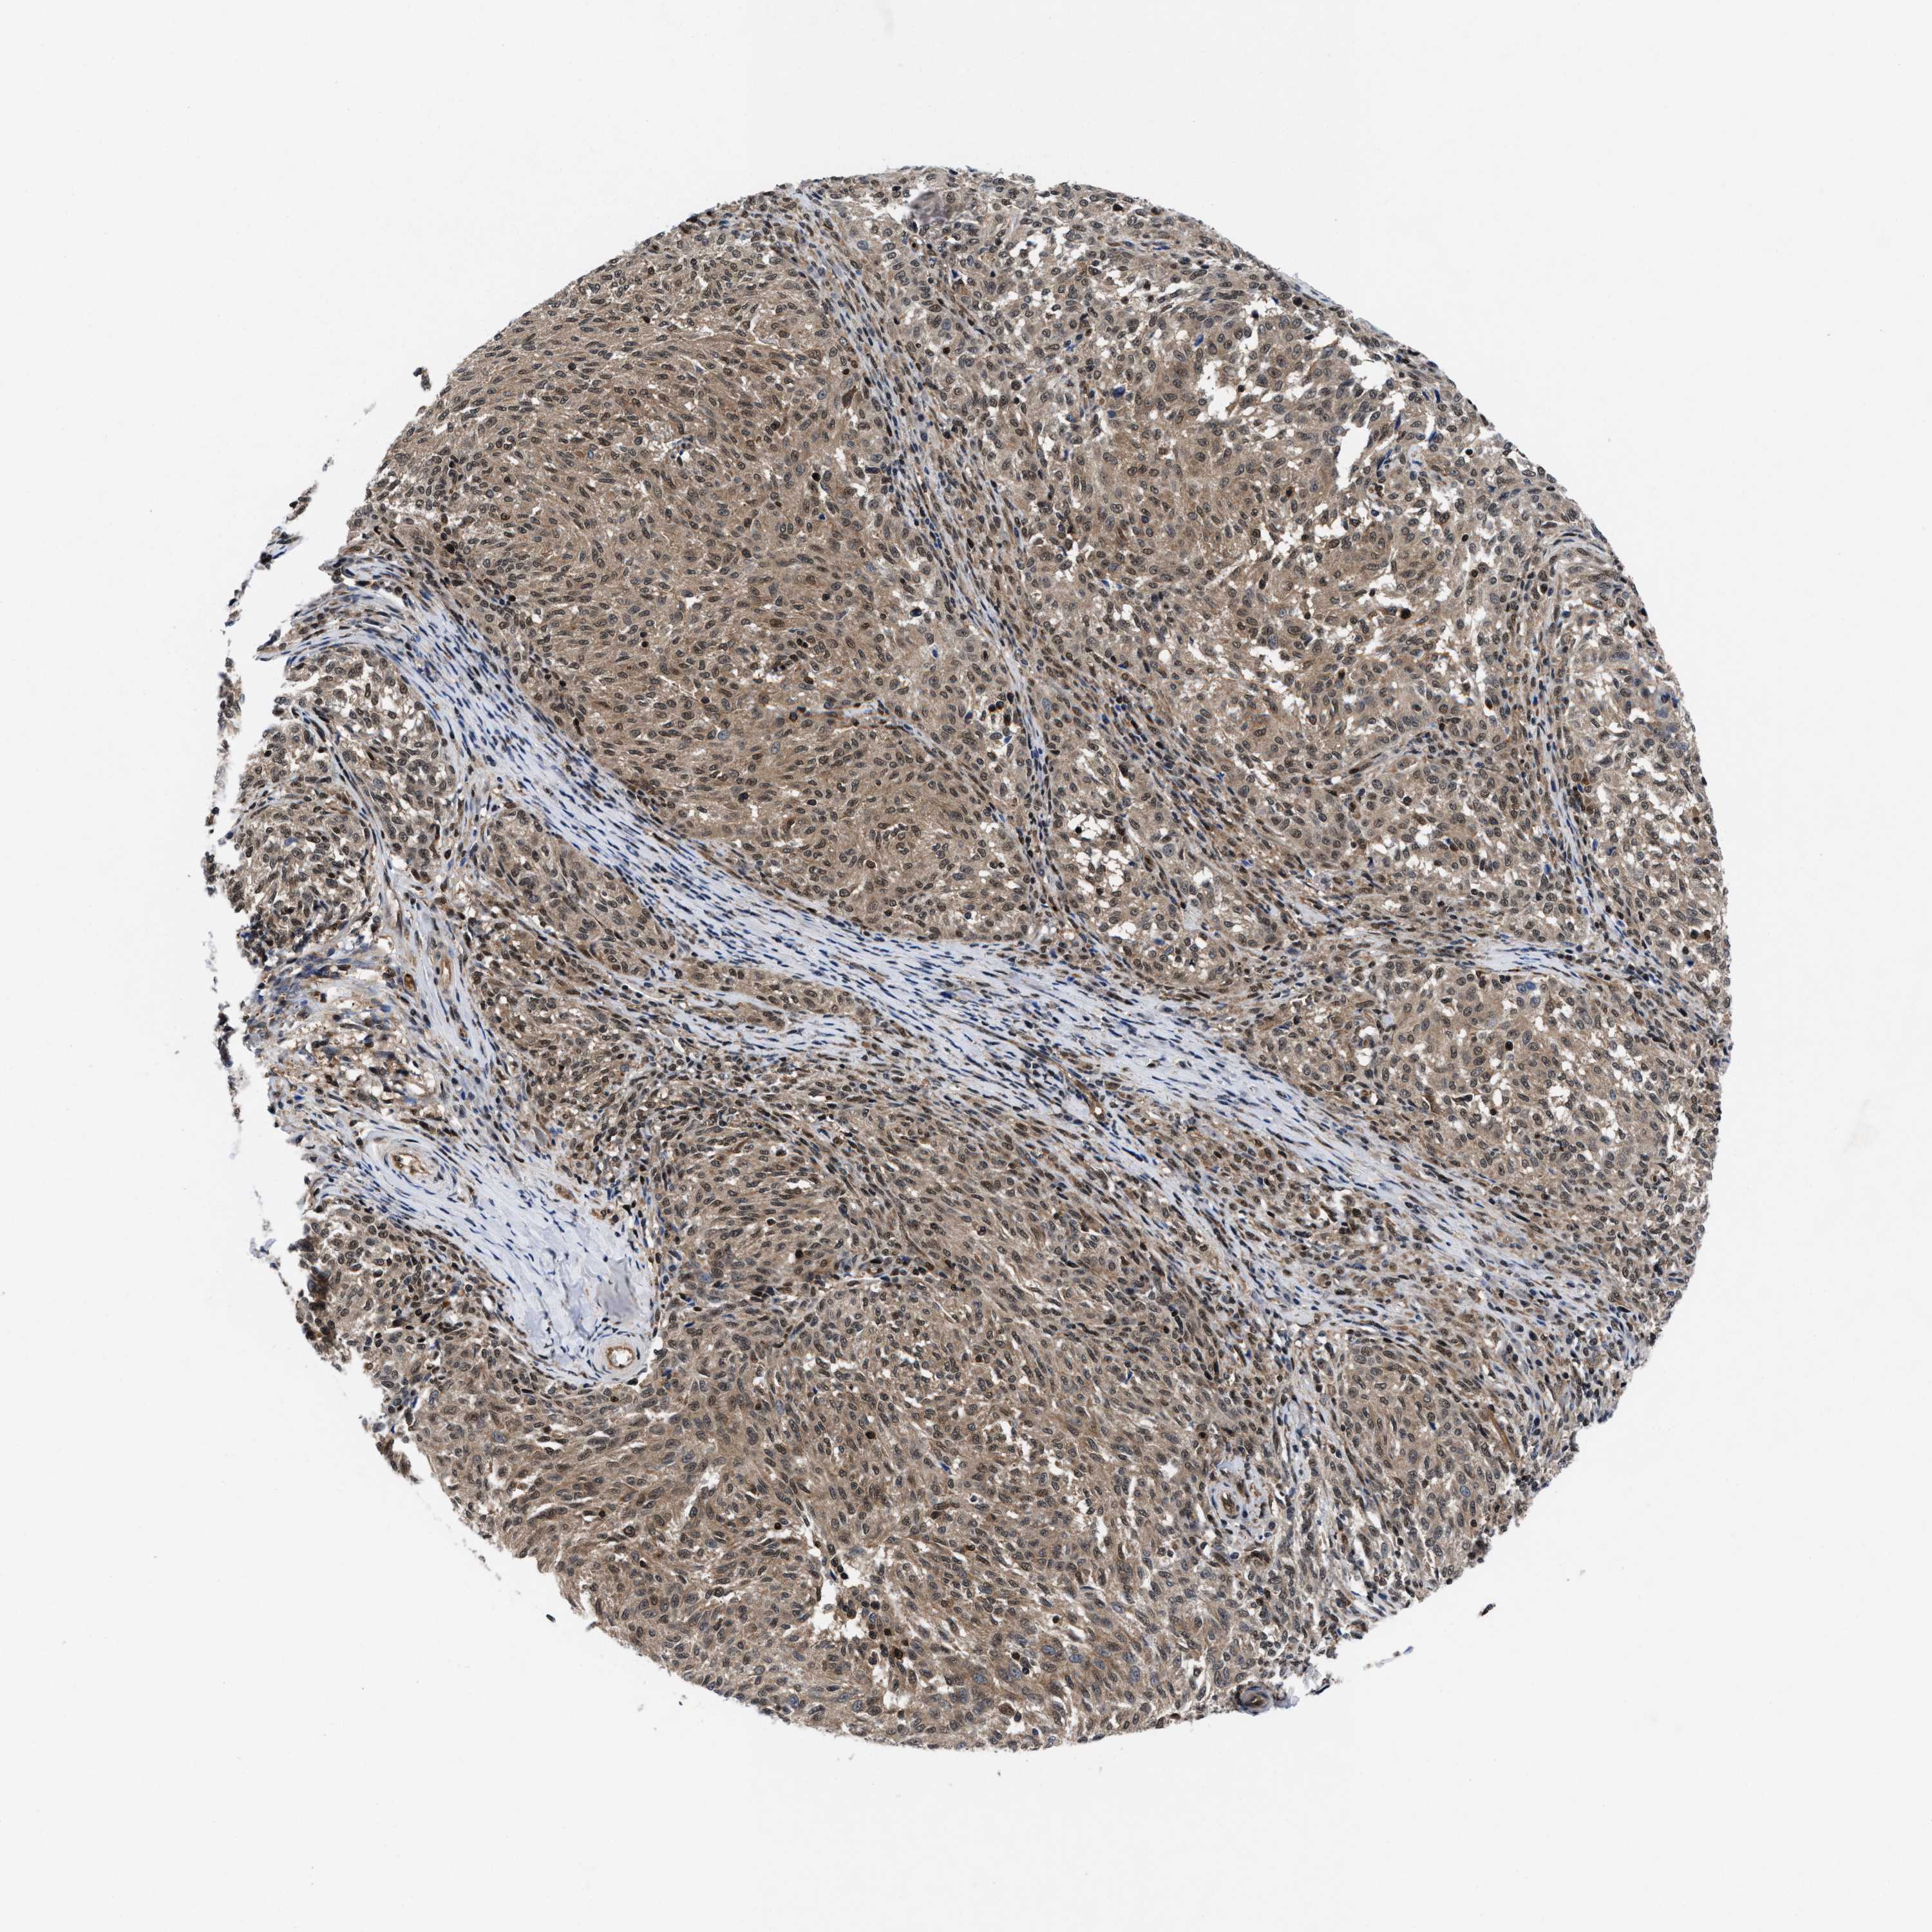

MELANOMA - Protein expressioni

A mouse-over function shows sample information and annotation data. Click on an image to view it in a full screen mode. Samples can be filtered based on level of antibody staining by selecting one or several of the following categories: high, medium, low and not detected. The assay and annotation is described here.

Note that samples used for immunohistochemistry by the Human Protein Atlas do not correspond to samples in the TCGA dataset.

Antibody stainingi

Antibody staining in the annotated cell types in the current human tissue is reported as not detected, low, medium, or high, based on conventional immunohistochemistry profiling in selected tissues. This score is based on the combination of the staining intensity and fraction of stained cells.

Each image is clickable and will lead to virtual microscopy that enables deeper exploration of all samples and also displays staining intensity scores, fraction scores and subcellular localization as well as patient and tissue information for each sample.

HPA022434

HPA022953

HPA022959

HPA028758

CAB007783

Staining

High

Medium

Low

Not detected

Intensity

Strong

Moderate

Weak

Negative

Quantity

>75%

75%-25%

<25%

None

Location

Nuclear

Cytoplasmic/membranous

Cytoplasmic/membranous,nuclear

Malignant melanoma, NOS

Malignant melanoma, Metastatic site